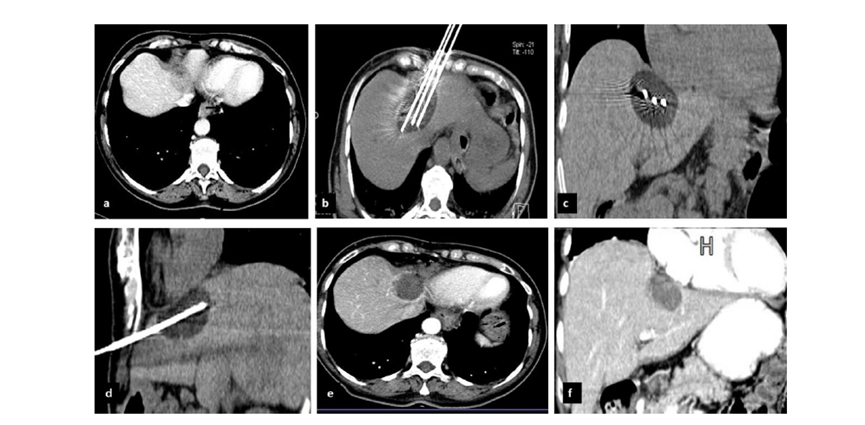

79 歲男性,肝轉(zhuǎn)移(結(jié)直腸癌)腫瘤的完全消融病例

( a ) 軸向 MRI 和 ( b ) 軸向 CT 顯示肝S8段有一個16mm的病灶,鄰近肝緣。( c )冷凍消融期間CT顯示放置了2個冷凍探針,低密度冰球包圍病灶。(d)術(shù)后1個月隨訪 CT顯示冰球?qū)?yīng)的壞死區(qū)域,未見復發(fā)。(e)術(shù)后6個月的CT,壞死區(qū)域縮小,未見復發(fā)。(f)與基線影像(g)相比,12個月后的FDG-PET/CT顯示未見FDG攝取。

62歲女性,肝轉(zhuǎn)移(卵巢癌)腫瘤的完全消融病例(a)軸向CT顯示病變位置毗鄰心臟和上腔靜脈(黑色箭頭)。(b)術(shù)中軸向CT掃描:使用三個冷凍探針。1個月后的軸向(e)和冠狀位(f)增強CT掃描顯示低密度區(qū)域,由于肉芽組織反應(yīng)引起的邊緣增強。

技術(shù)成功100%,92% 的病灶中觀察到腫瘤完全消融。16 名患者 (33%) 出現(xiàn)局部復發(fā)。10 名患者 (20%) 因局部復發(fā)或腫瘤消融不完全而接受二次冷凍消融術(shù)。

7名患者出現(xiàn)輕微并發(fā)癥,未發(fā)現(xiàn)膿腫形成、膽漏、膽汁瘤或血液學變化。冷凍消融可安全、有效治療毗鄰重要臟器的原發(fā)性肝臟腫瘤和肝轉(zhuǎn)移瘤患者,有效控制腫瘤局部進展,使患者生存獲益。我國作為肝癌大國,對于肝癌的治療一直給予高度重視。基于專家共識和相關(guān)文獻研究結(jié)果顯示,冷凍消融技術(shù)具有高效、低成本、創(chuàng)傷小、適應(yīng)證廣、并發(fā)癥相對較少等優(yōu)點,可有效延長患者生存期、提高生活質(zhì)量、降低患者經(jīng)濟負擔。因此,冷凍消融技術(shù)在肝癌的應(yīng)用中有著極高的潛力和廣泛的發(fā)展空間。